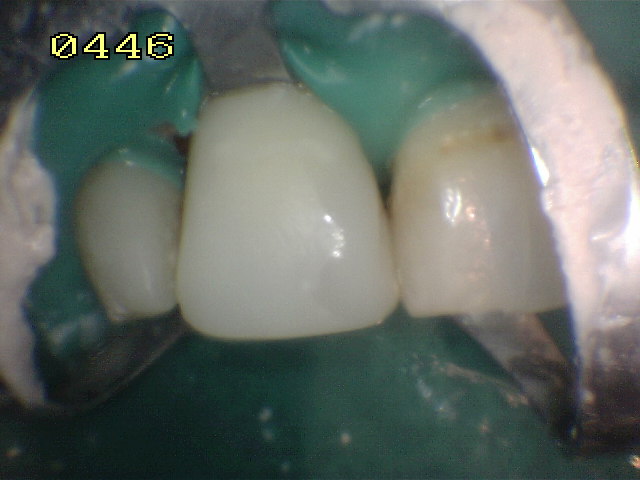

Caso terminado con

resina de fotocurado A2 |